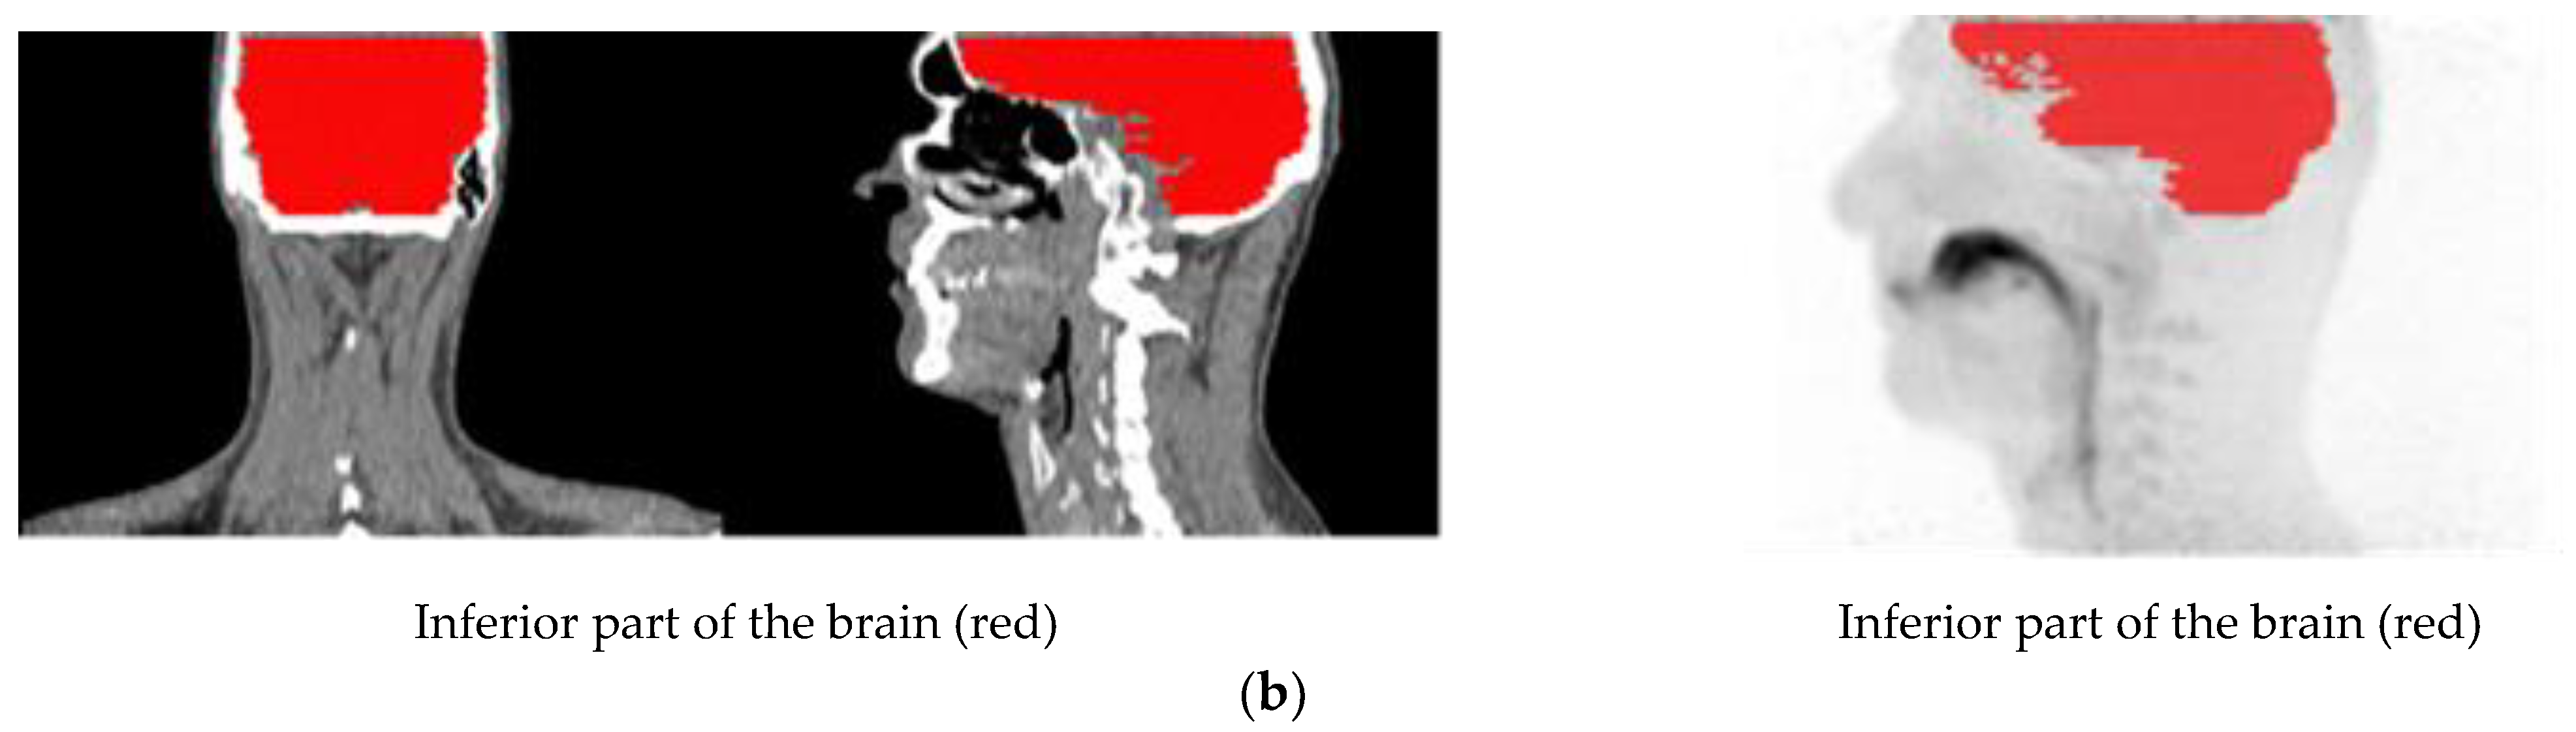

Volumes of interest (VOIs) were outlined on summation images from 20 s until the end of the scan. In part A, the outlined VOIs represented: lung, deep lung, trachea, primary-secondary bronchi, oral cavity, and oesophagus. Furthermore, the inferior part of the brain was delineated for four scans, two each for freebase and nicotine lactate.

The lung, deep lung, and trachea were delineated using the anatomical information from the ULDCT scan. Primary, secondary bronchi, oral cavity, and oesophagus were outlined on a combination of the individual’s ULDCT and [11C]nicotine PET summation images. The delineated VOIs were subsequently transferred to the corresponding individual dynamic [11C]nicotine PET scan for the generation of time-activity curves (TACs). Hermes software (GoldLx, version 2.8.0.0 and PDR, version 4.0.1), was used for VOI delineation and extraction of time-activity data. An example of the resulting VOIs is shown in Figure 6. For a detailed description of outlining of VOIs, see supplementary material.

Figure 6.

(a) Illustration of the delineated VOIs on mouth and lung scan. (b) Illustration of the delineated VOIs on inferior part of the brain.